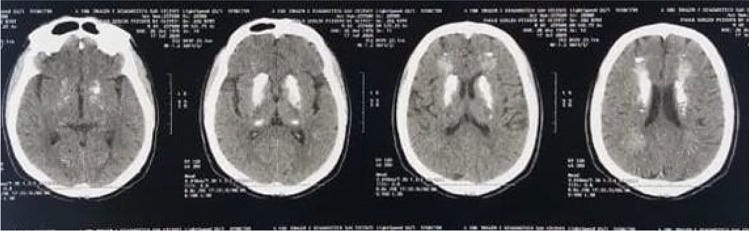

Brain CT showing bilateral brain calcifications

In a recent manuscript published in Neurological Sciences, Demir (2020) attributed the incidental findings of bilateral brain calcifications in neuroimaging of a patient during SARS-CoV-2 infection to a condition known as Fahr’s syndrome. In this case, there was an important contribution, since neurological symptoms enabled the incidental diagnosis of a rare neurological disorder.